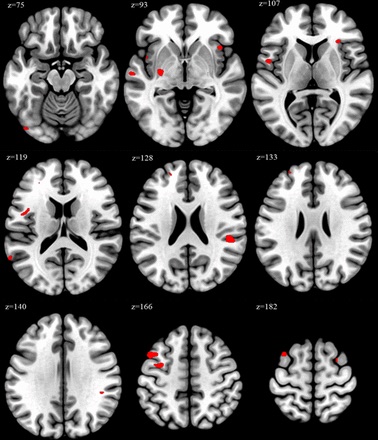

Науковці використали техніку нейровізуалізації для аналізу об’єму мозку досліджуваних медпрацівників. Це дало змогу визначити та порівняти відмінності в рівнях сірої речовини в різних ділянках мозку.

«У людей, які працювали 52 або більше годин на тиждень, спостерігалися значні зміни в ділянках мозку, пов’язаних із когнітивною функцією та емоційною регуляцією, на відміну від учасників, які працювали стандартні години», — заявили дослідники.

Ділянки мозку, де було зафіксовано збільшення об’єму, включають середню лобову звивину, що відіграє ключову роль у когнітивних функціях, увазі, пам’яті та мовних процесах, а також частку, яка залучена до емоційної обробки, самосвідомості та розуміння соціального контексту.

Дослідники вважають, що їхні висновки свідчать про «потенційний зв’язок» між збільшенням робочого навантаження та змінами в цих частинах мозку.